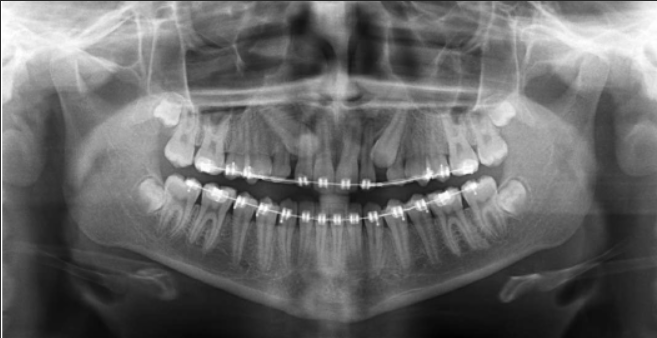

Treatment depends on age, position, and severity. The most common approach involves surgical exposure of the tooth, often followed by orthodontic guidance to help it erupt into its proper position.

We use 3D imaging to locate the tooth precisely and work closely with your orthodontist to coordinate care. The procedure is usually done under sedation to ensure a smooth experience.

We use advanced 3D imaging technology to locate the tooth precisely and carefully plan the procedure. This ensures minimal disruption to surrounding teeth and bone, allowing for safer and more predictable outcomes. Our oral surgeons work closely with your orthodontist to coordinate care and monitor progress throughout the treatment. Procedures are typically performed under sedation or local anesthesia to provide a comfortable and stress-free experience.